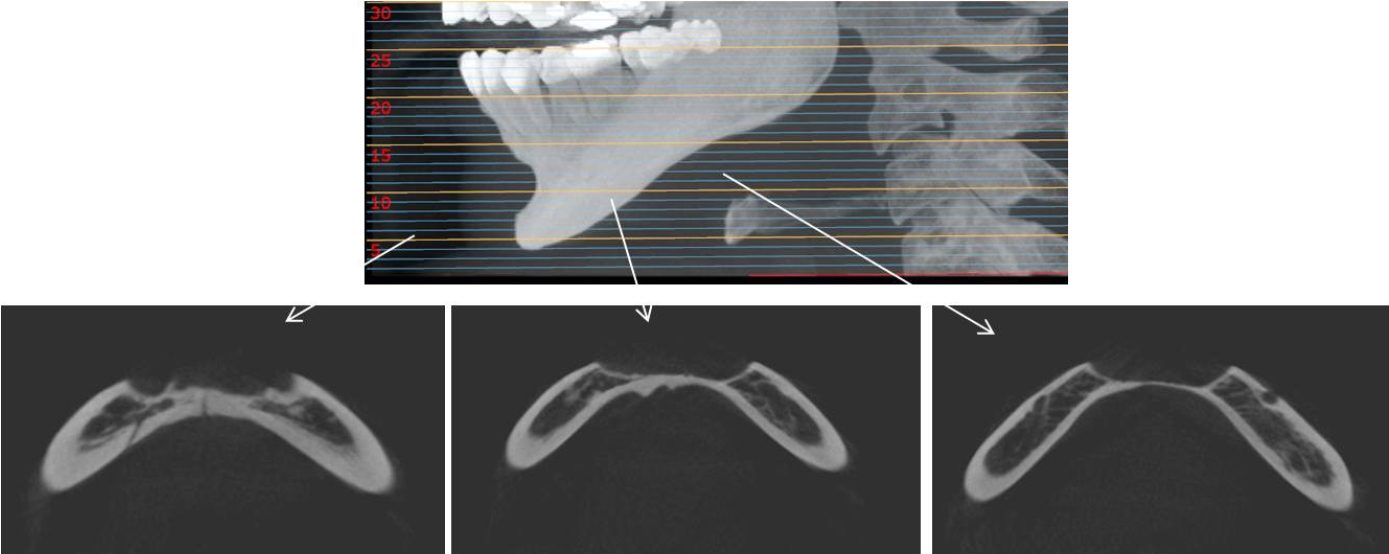

32세 여성 환자의 파노라마방사선영상에서 하악 전치부 낭이 관찰되어, 정확한 진단을 위하여 본원에 의뢰되었다. 특별한 임상증상은 없었다. 파노라마방사선영상에서 하악 우측 제1소구치에서 좌측 제1소구치 치근하방에 경계가 명확하고 피질골성 변연을 가진 타원형의 방사선투과상이 관찰되었다(Fig. 1). 방사선투과상은 해당치아들과는 무관하여 치근단낭이 배제되었고, 단순골낭의 가능성을 염두에 두고 콘빔CT 검사를 시행하였다. 콘빔CT에서 중심성 골내 병소가 아닌 악골의 순측에서 설측으로 함몰된 변연성 병소가 관찰되었다(Fig. 2). 병소의 경계는 매우 평활하였고, 단면상에서는 넓은 접시모양처럼(Fig. 3), 악골 절단면상에서는 반달모양처럼 함몰되어 있었다(Fig. 4). 설측 피질골은 비박되어 있었으나 천공은 관찰되지 않았다. 함몰된 부위는 공기가 아닌 연조직의 방사선투과상으로 채워졌으나, 콘빔CT에서는 대조도가 낮아서 연조직간의 감별이 가능하지 않았다(Fig. 5). 관찰된 턱 끝 부위의 골 함몰이 해부학적 변이인지 아닌지를 감별하기 위하여 환자의 과거 병력을 알아보았다. 환자는 2년 전에 턱 끝 부위에 미용 필러 시술을 받았다고 하였다. 방사선영상소견과 문진결과를 토대로, 미용 필러와 관련된 골흡수를 의심하였다. 이후 외과적으로 미용 필러 제거와 함몰된 부위에 골이식이 시행되었다. 수술 중에 육안으로 남아있는 미용 필러와 작은 석회화 물질들이 확인되었다. 수술 후 생검에서 다핵거대세포와 결절석회화가 관찰되었고, 피부석회화(calcinosis cutis)가 의심된다는 결과를 받았다. 이상의 술 전 검사 및 술 후 소견을 종합하여, 파노라마방사선영상에서 관찰된 방사선투과상은 치성낭이나 해부학적 변이가 아니고 미용 필러에 의한 하악골 순측 골흡수로 최종 진단되었다.

Cone-beam computed tomographic axial view shows a well-circumscribed peripheral depression with smooth borders and a corticated margin.

Cone-beam computed tomographic cross-sectional view of the mandible clearly demonstrates a peripheral bone depression extending from the labial to the lingual cortical plate.